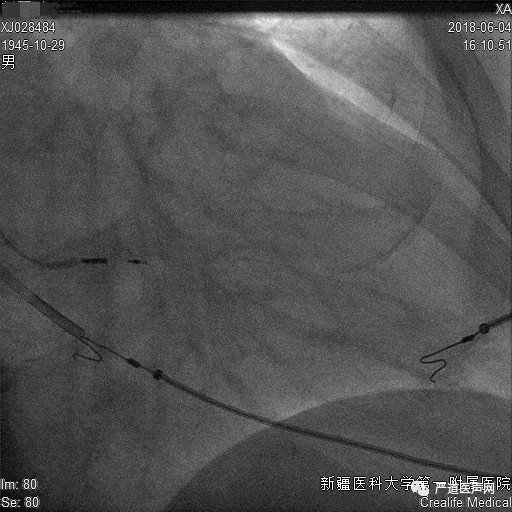

72岁男性,10个月前无明显诱因出现胸闷,伴有气短,夜间阵发性呼吸困难,曾在当地医院诊断为心功能不全,服药后间断出现主诉症状,有冠心病病史,近10余天症状加重。入院后心脏超声示左房、左室腔增大,左室壁节段性运动减弱并左心功能不全,EF 34%。心电图示窦性心律,LBBB,QRS 160ms,偶发室早,完全性左束支传导阻滞。诊断为急性失代偿性心力衰竭,心功能IV级。冠状动脉粥样硬化性心脏病,缺血性心肌病,心律失常,偶发室早,完全性左束支传导阻滞,II型糖尿病。

手术要点:

脉状静脉逆行造影显示侧静脉分支,考虑侧静脉细小不适合植入四极电极,遂决定行后侧静脉造影,侧后静脉造影仍旧不理想。综合血管情况考虑,尝试鞘中鞘造影靶血管,多次尝试后电极仍旧无法进入靶血管,继续递送双导丝增加支撑力后发现无效,使用球囊扩张开口狭窄处,扩张后重新递送PTCA导丝,发现无法找到开口处,行静脉造影发现靶血管开口处闭合,只能考虑更换靶血管,尝试后侧静脉,电极仍旧未能走至远端,同时测试电极参数不理想。讨论后决定放弃左室电极植入,行左束支起搏,使用C315HIS鞘+3830电极定位希氏束位置,然后用另外一根3830从右束支穿过室间隔到左束支固定。

鞘中鞘靶血管造影